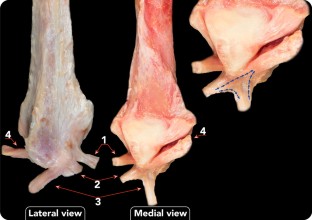

Connections were found in all cases between the ATFL and PTFL, the ATFL and CFL, and the CFL and PTFL. Connections between ATFL and PTFL were not homogeneous. Although connections between the ATFLif and PTFL were noted in all cases (40), only 17 ankles (42.5%) had connections between the ATFLsf and PTFL. The amount of fibres of connection was also variable.

Connections between the three components of the lateral collateral ligament of the ankle may be observed from the medial aspect of the ankle, and this may have important implications for arthroscopic lateral ligament repair.